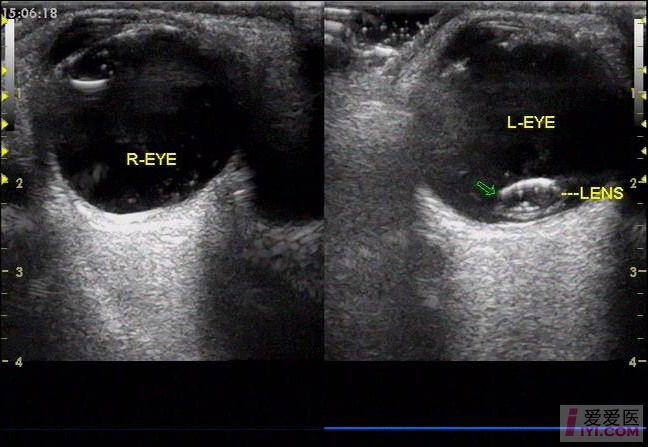

晶状体半脱位

【白内障讨论】双眼晶体半脱位